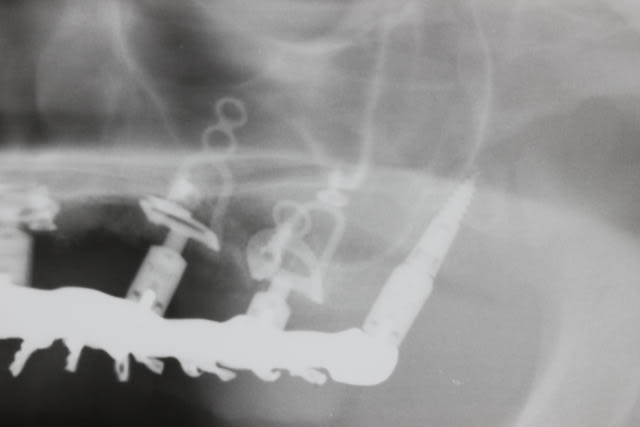

Le dentascan de la mandibule pour que vous compreniez mieux la difficulté...quais impossible de la considérer en cylindres même en déplaçant le NDI vous n avez aucune hauteur exploitable... Même des lame de Likow n y passent pas et les sous périostés sont interdits en Europe

J ai perdu mes deux foutus cylindres et ai dû les remplacer par deux double disk...et changer les deux mono disk du secteur droit

Et oui l implanto basale n est pas non plus un long fleuve tranquille

1. Les deux distaux pour s ancrer le plus possible derrière car zone solide en distal... Il est vrai que les zones des 7 paraissent bien la pano mais le modèle 3D de Materialise ne montrait pas autant d os que ça donc j ai choisi distal car on mieux se caler ds des corticales

2. Oui sans doute après coup pourquoi des cylindres de 8mm en diamètre 4.75 ... mais bon voilà les deux disk de 11 par 9 mm je les ai bloqués à coup sûr et distalement en plus ce qui est plus solide et tant pis si les 7 sup sont des inter de bridge

3. De plus on comble en vestibulaire avec du nanobone ou du MP3 ds la zone des disks d où cette image à laquelle les implantos basaux sont habitués : on a l impression qu il y avait plus d os et qu on aurait pu faire autrement... Reagarde Alapex vient de passer les photos du materialise